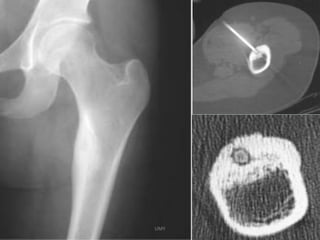

Radiological findings : Radiolucent nidus ( 1.5 cm)

Diagnosis : Tc99 bone scan – Inc uptake

“Headlight in fog “ & “Double – density sign “

CT – BULLS EYE appearance

- Pain iselicited by local pr. - O.O is suspected in spine when a pt < 30 yrs complains of constant back pain , when spine is stiff and scoliotic & SLRT is positive with no signs of nerve root compression. Radiological findings : Radiolucent nidus ( 1.5 cm) with reactive sclerosis in cortex , DD : Osteoblastoma , Non-suppurative osteomyelitis of garre , Brodies abscess, Stress # , Diagnosis : Tc99 bone scan – Inc uptake “Headlight in fog “ & “Double – density sign “ CT – BULLS EYE appearance UMY